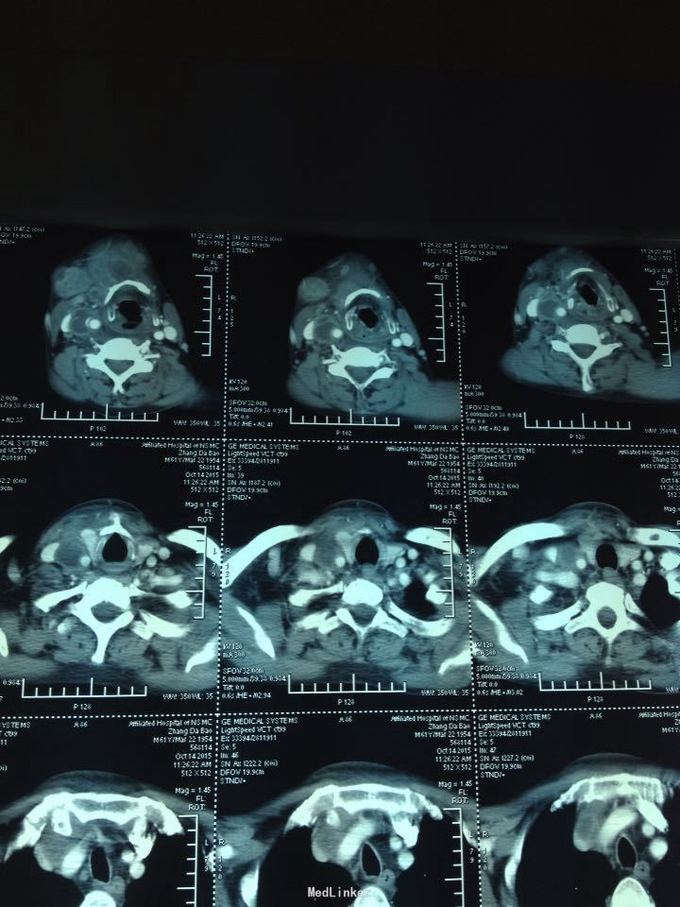

颈部肿痛10多天。10多天前无明显诱因出现颈部及颌下疼痛,肿胀明显,吞咽受限,无伴明显呼吸困难。无高热、寒战等。未特殊处理,上述症状渐加重。

双侧颈部肿胀明显,皮肤稍充血,皮温较高,可触及波动感,压痛明显,右侧为甚,咽部黏膜充血肿胀明显。

颈部多发脓肿。入院后完善相关检查,给予抗感染、对症支持治疗,并于急诊全麻下行颈部脓肿切开引流术,术中分离右侧颈动脉鞘,充分分离脓腔,充分引流。